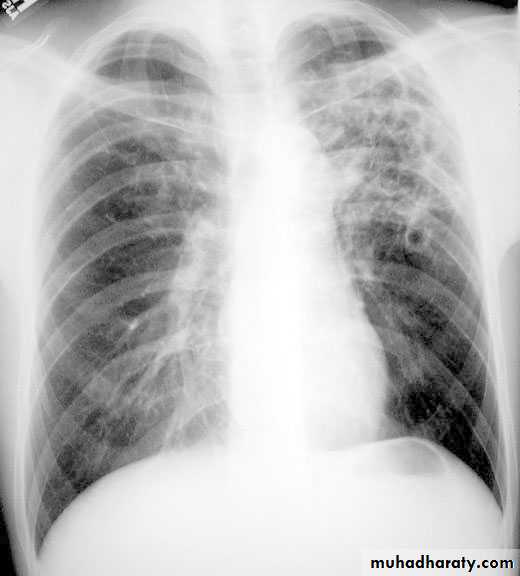

Post primary tb

TB lung

Tuberculoma mycetoma